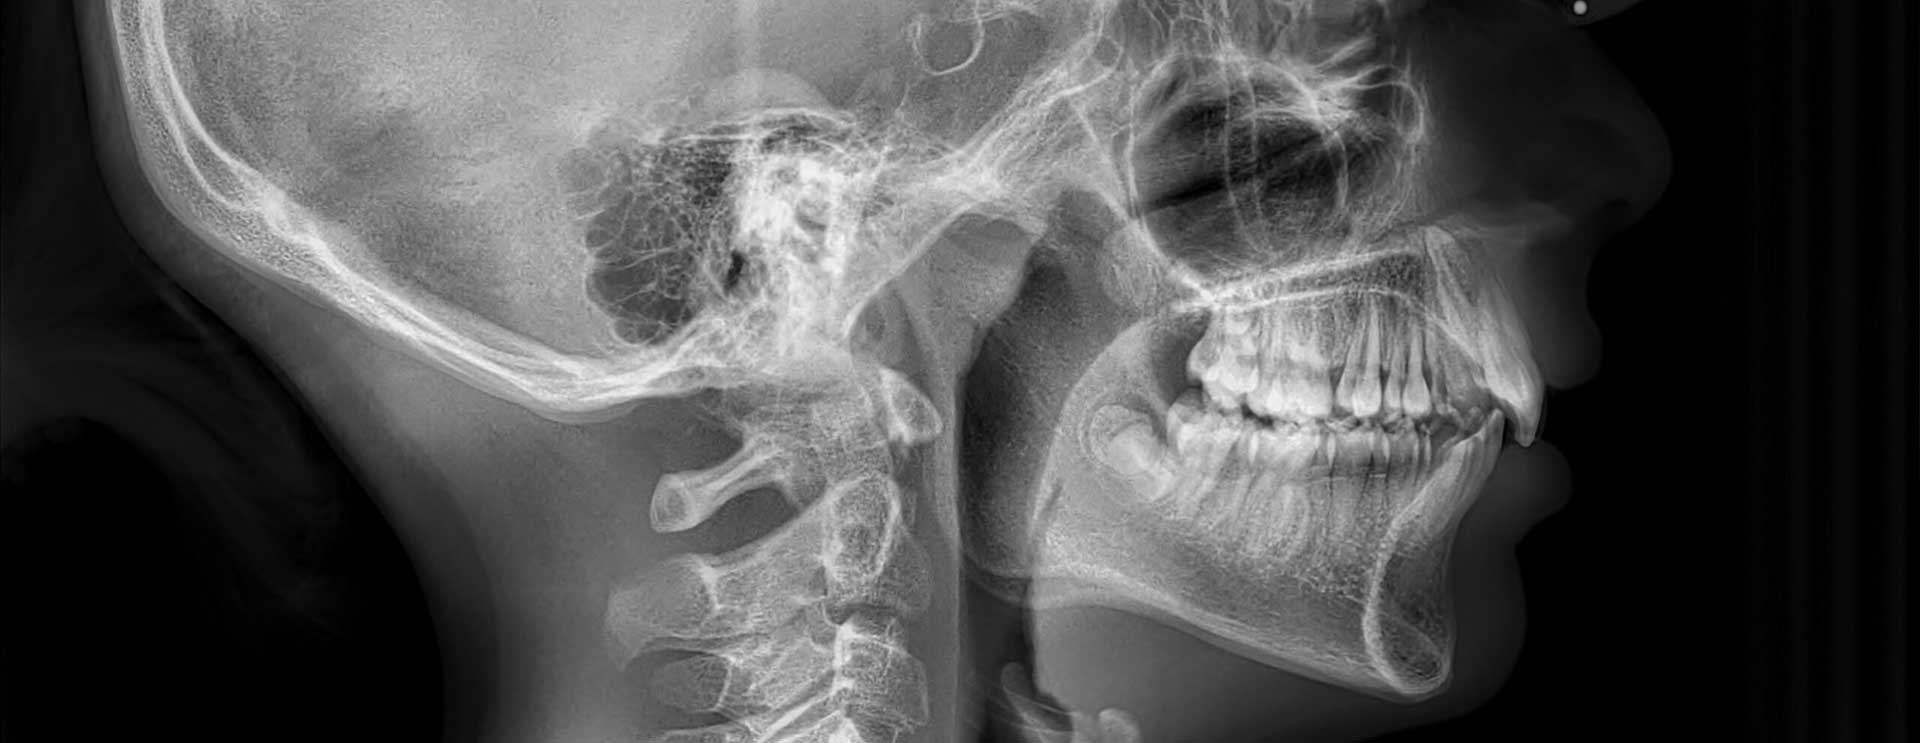

צילום צפלומטרי

צילום צפלומטרי הוא צילום רנטגן בקרינה מינימלית המשמש את הרופא האורתודנט לבנות תוכנית טיפול מדויקת ומיטבית של יישור שיניים. במהלך הצילום מתועד הפרופיל של המטופל ממבט צד של הגולגולת, וכן מתועדות הרקמות הרכות של האף והסנטר. לאחר פענוח הצילום, מקבל האורתודנט תמונה מלאה על מיקום השיניים והיחס ביניהן, מנח הלסת העליונה אל מול התחתונה, מיקום הלסתות ביחס לבסיס הגולגולת ושיקוף מלא של השיניים החותכות הקדמיות ביחס לעצם התומכת בהן. מידע חיוני זה מאפשר לרופא לבנות עבור המטופל תוכנית טיפול יישור שיניים פרטנית ומיטבית.

צילום צפלומטרי אורך מספר שניות בודדות ואינו כואב. הוא מבוצע באמצעות מכונת רנטגן מתקדמת בקרינה מינימלית ולא מזיקה, המאפשרת לצלם את הראש והפנים מכמה זוויות במטרה לשקף את מצב השיניים והלסת. הצילום אינו פולשני ולא מצריך הכנסת מכשור אל תוך חלל הפה. הוא עושה שימוש במצלמה המבצעת סריקה חיצונית של סביבת הראש והפנים במשך כמה שניות רציפות ומבוצע לקראת תהליך יישור שיניים, ולעיתים גם במהלכו.